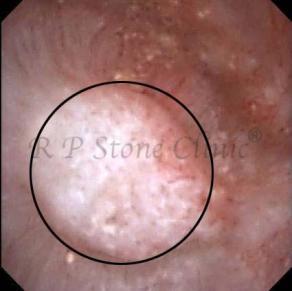

Kidney stone is a solid mass of CRYSTALS. It is the process of crystallization which initiates the formation of kidney stones. This happens in nephrons or units of kidney. Once a small crystal is formed, it can both grow & unite with other crystals leading to the formation of small concretion which eventually forms a stone. Once these large crystals detach from the collecting ducts, the process of stone formation starts in the renal collecting system. A recurrent kidney stone former is advised to know a little bit about something known as Randall’s plaque. Alexander Randall discovered plaques on the renal papillae eight decades back based on examination of 1154 pairs of autopsied Kidneys. He described these renal papillary lesions as cream colored or milk patch areas composed of calcium phosphate & calcium carbonate. These plaques could act as NIDUS for formation of KIDNEY STONE. Calcium Oxalate stone can form on this nidus & then detaches from this plaque to become a free floating stone in the collecting system of kidney

These images are taken as snap shots from the video recording of RIRS Surgery done at our hospital. These are Randall’s Plaques seen with Digital FLEX XC & Digital FLEX XC S. The cream or whitish patches are seen on the tips of RENAL PAPILLAE as seen in images below.

Randall’s Plaques may lead to the formation of Stones.

Those kidney stone patients who have Randall’s Plaques in their kidneys are more likely to form stones again (Recurrent Stones).

Stone Patients in whom Randall’s Plaques are detected at the time of RIRS Surgery should undergo regular ultrasound examination for early detection of stones.

Patients of Stones with Randall’s Plaques in their Kidneys should drink plenty of fluids in addition to Orange Juice & Lemonade.